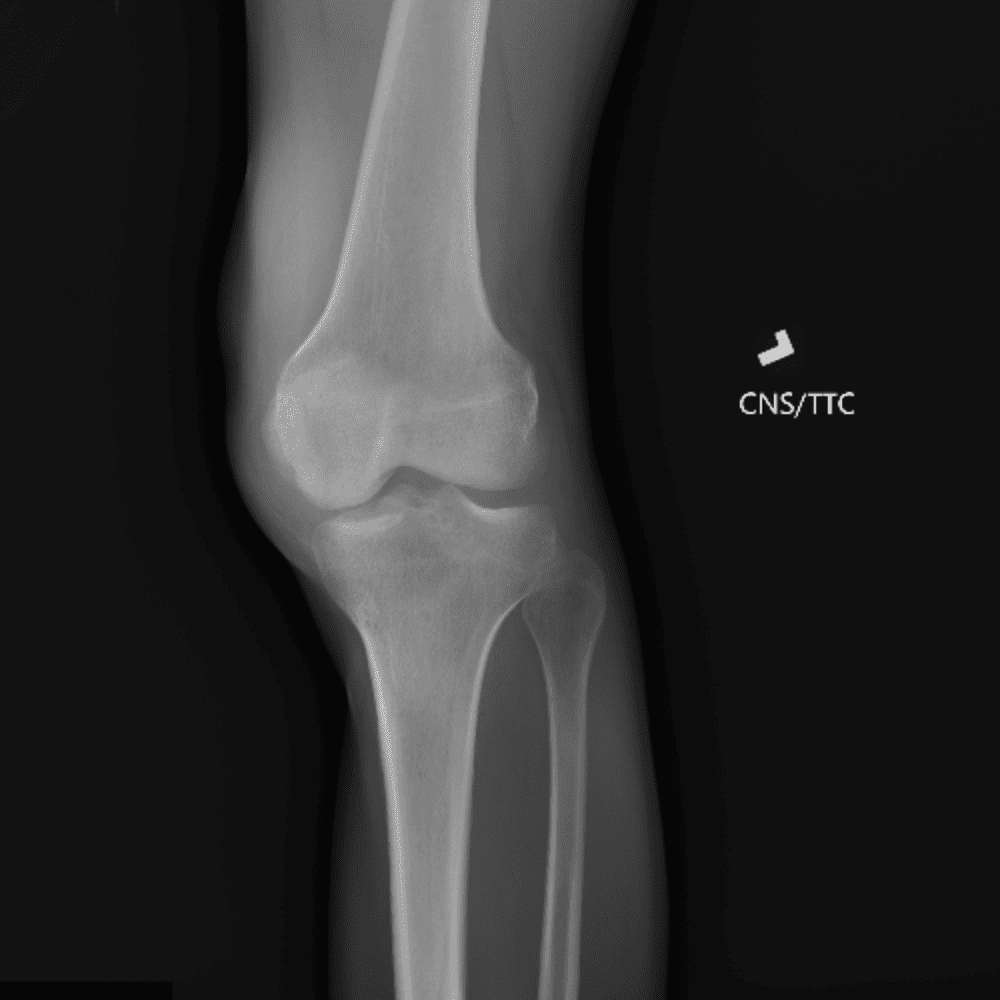

Simula o plantão incluindo casos sutis ou difíceis e alguns normais.